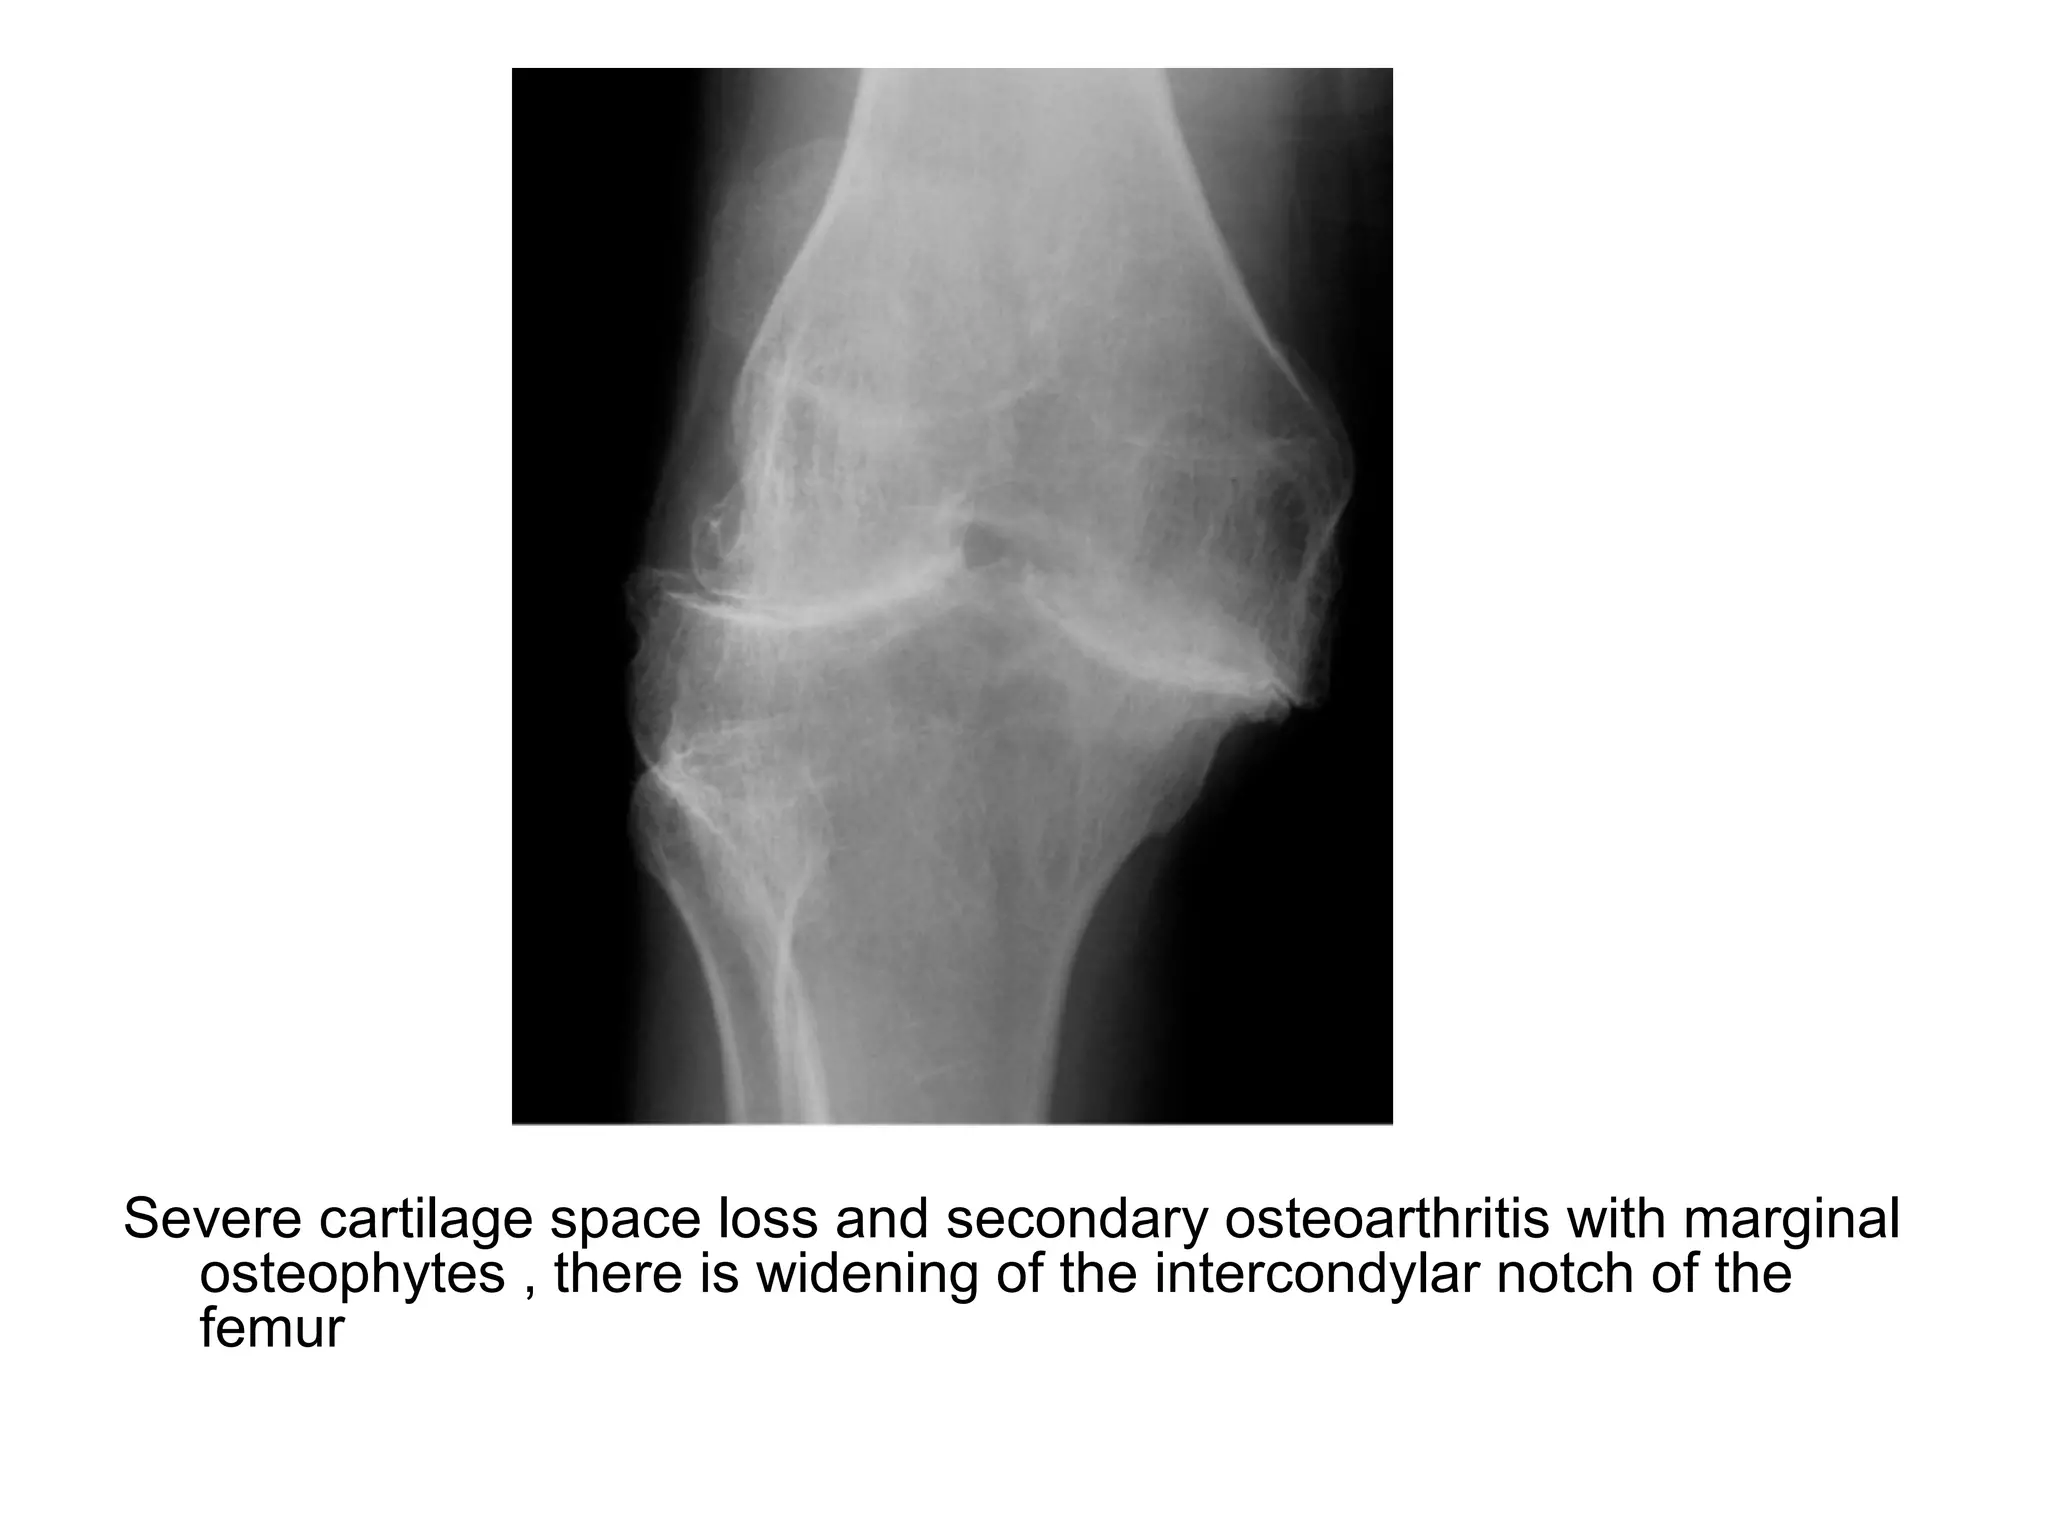

Severe cartilage space loss and secondary osteoarthritis with marginal

osteophytes , there is widening of the intercondylar notch of the

femur